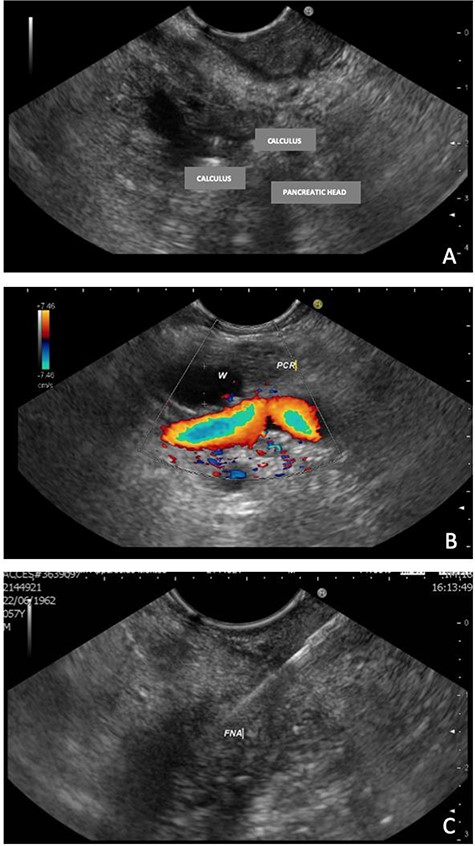

EUS, 15 days after, suggested chronic inflammation of the pancreas with multiple stones (≤9.0 mm) in the main pancreatic duct leading to ascending dilatation and tortuosity of the main pancreatic duct. Moreover, it presents a solid formation in the head/uncinate transition on its dorsal face (Fig. 2). A biopsy was performed and the cytologic result was inconclusive.

EUS—solid formation in the head/uncinate transition on its dorsal face. (A) EUS demonstrating multiple calculi and the pancreatic head; (B) EUS with evidence of a 7-mm Wirsung duct (PCR = pancreas; W=Wirsung duct). (C) Fine needle aspiration (FNA) of the nodular lesion.